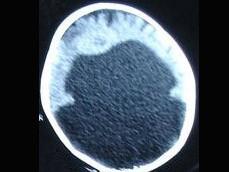

问题 9个月女婴,头颅迅速增大,四肢肌力下降,CT表现如图,首先考虑以下哪个疾病 ( )

选项 A、脑灰质异位 B、无脑回畸形 C、Dandy-Walker综合征 D、前脑无裂畸形 E、胼胝体发育不全

答案 D